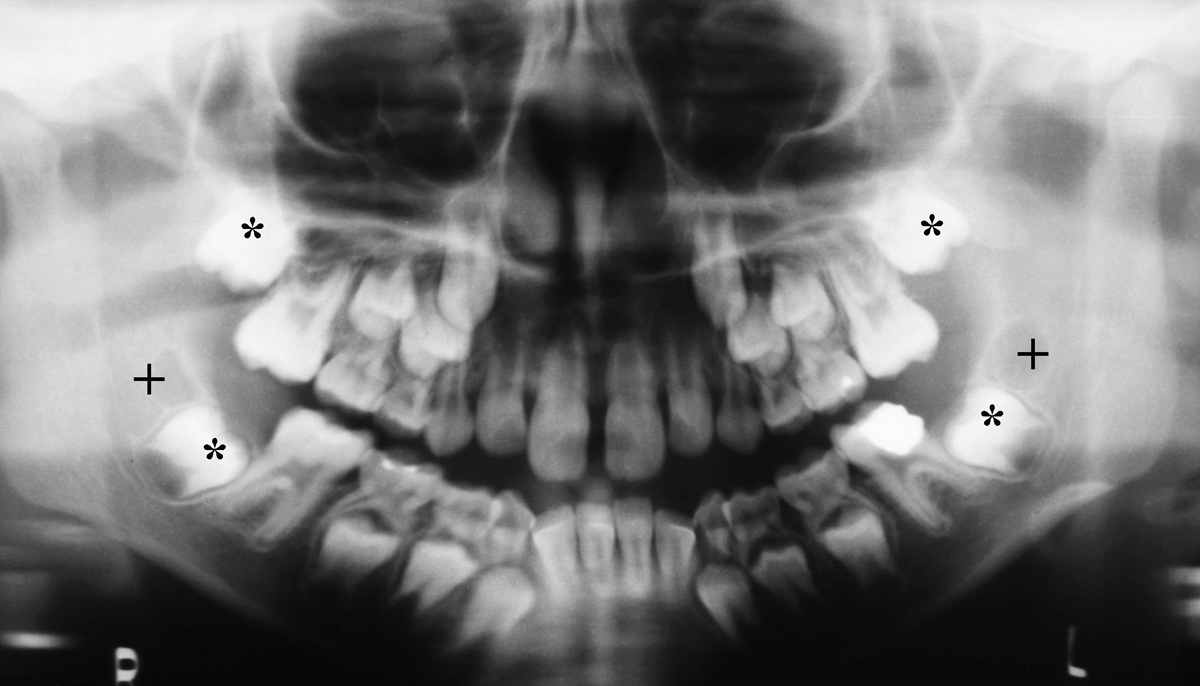

Stages of Dentition

Three separate stages of dentition occur in humans (figure: stages of dentition). The earliest stage lasts up until approximately six years of age with the mouth containing 20 temporary deciduous teeth. During the second stage from ages 6 to 21, both the deciduous temporary teeth and the permanent teeth replacing them are present in the oral cavity. The timing of permanent tooth eruption varies according to the specific tooth. The third and final stage of dentition is observed in the adult. Commonly, this stage demonstrates 32 teeth, containing three molars, two premolars, one cuspid, and two incisors in each of the four quadrants in the mouth. Although 20 deciduous teeth and 32 permanent teeth is the most common presentation, patients may vary in their number of teeth. Adontia is the developmental absence of teeth, and may be total or partial. Extra teeth are a more common variant, particularly in the incisor region, and are referred to as supernumerary teeth.

Mixed dentition in a child with permanent teeth plus retained primary teeth. The + marks developmental follicles for the third molar and the * marks permanent second molars. |